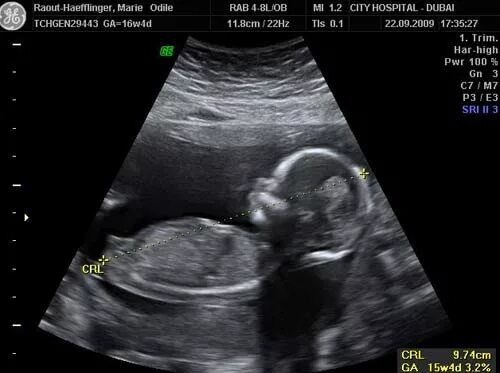

13 недель какой размер